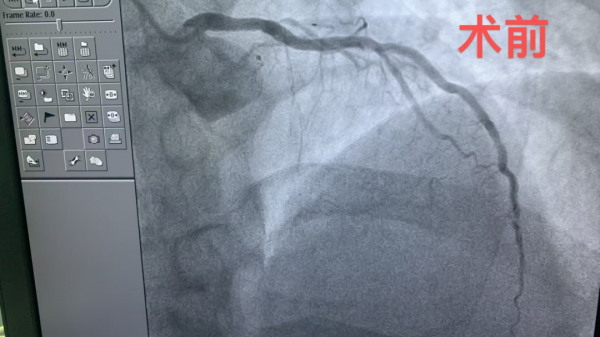

1、39岁男性,前降支闭塞,行血栓抽吸+冠脉内溶栓。

2、71岁男性,右冠闭塞,行药物球囊扩张成形术。

3、69岁男性,双支病变,行介入治疗。